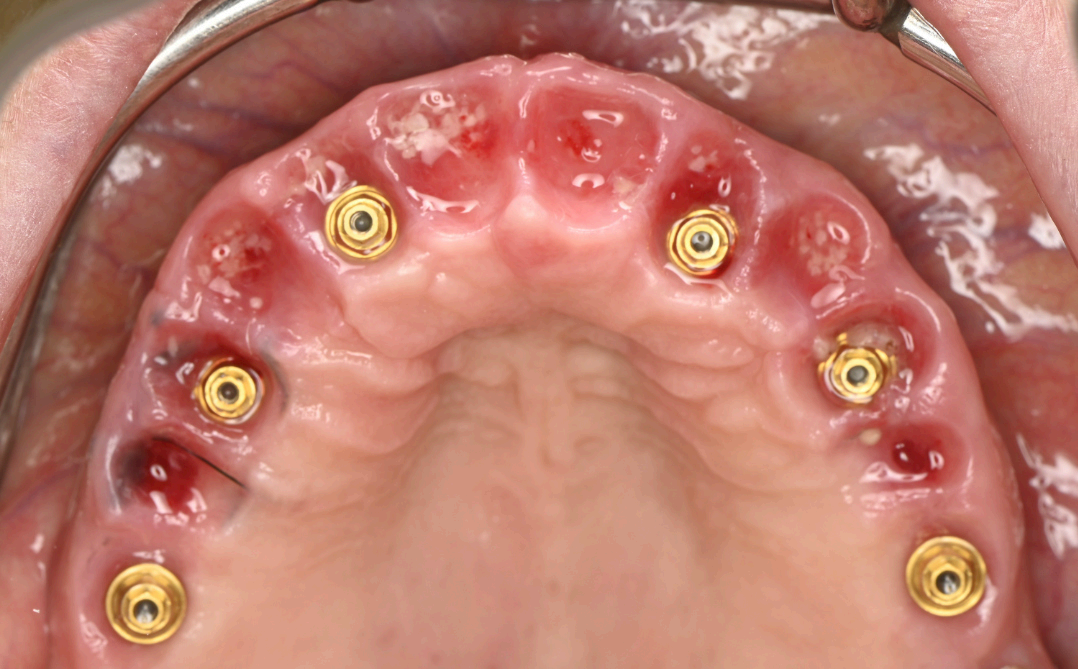

Following implant placement, intraoral photogrammetry was performed using the Shining3D Elite scanner. Scan markers were attached to the MUAs, and their positions were captured with high precision (Fig. 2.4, 3.4). Multiple scans were acquired, including the maxillary arch (Fig. 3.1), the fxation bar from the stackable guide (Fig. 3.2), the MUAs (Fig. 3.3), and the surrounding soft tissues (Fig. 3.5). The photogrammetry data was merged with conventional intraoral scans, using the fxation bar as a fduciary to align all datasets accurately (Fig. 3.7). A heat map generated in the software confrmed the precision of this alignment, with minimal discrepancies across the arch (Fig. 3.7). The scan markers were then converted to implant-specifc analogs compatible with the chosen implant system (Fig. 3.6).

Group 3: Digital Scanning Fig. 3.1: Full maxillary scan prior to merging. Fig. 3.2: Scan of the fxation bar from the stackable guide as a fduciary reference. Fig. 3.3: Scan showing MUAs in position. Fig. 3.4: Photogrammetry scan markers captured intraorally. Fig. 3.5: Composite scan integrating photogrammetry markers with soft tissue data. Fig. 3.6: Conversion of scan markers to implantspecifc analogs. Fig. 3.7: Heat map illustrating scan alignment accuracy post-merging. Fig. 3.8: Design of the provisional prosthesis with screw channel holes.